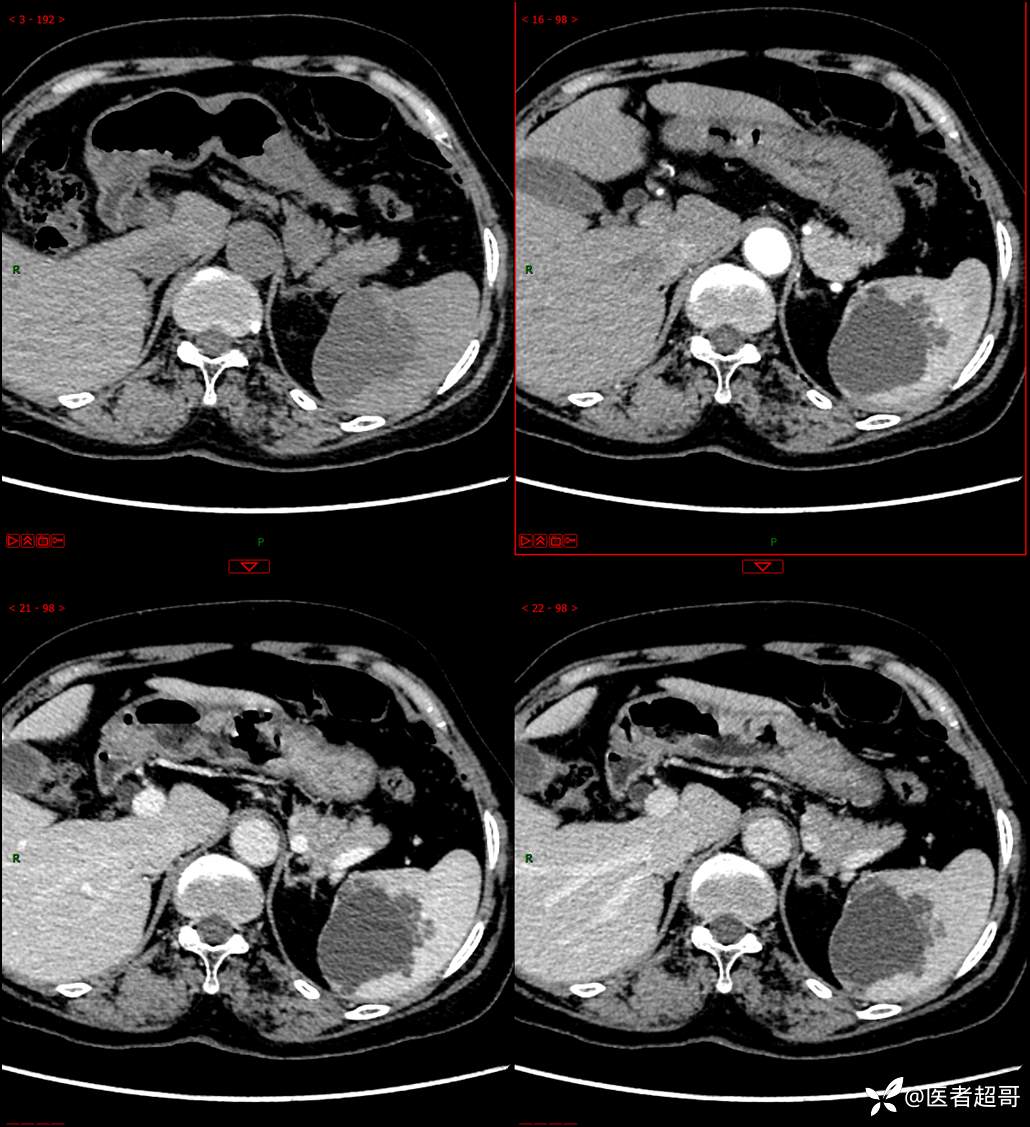

现病史:患者9天前于市人民医院查体时发现脾脏肿物,未行处理,后于我院门诊查,上腹部CT平扫+强化:脾脏占位,考虑良性,囊肿?脉管源性病变?患者诉平素无异常不适。现患者为求进一步诊疗,门诊遂以“脾肿物”收入院。患者自患病以来,神志清,精神可,饮食、睡眠可,大小便正常,体重未见明显变化。